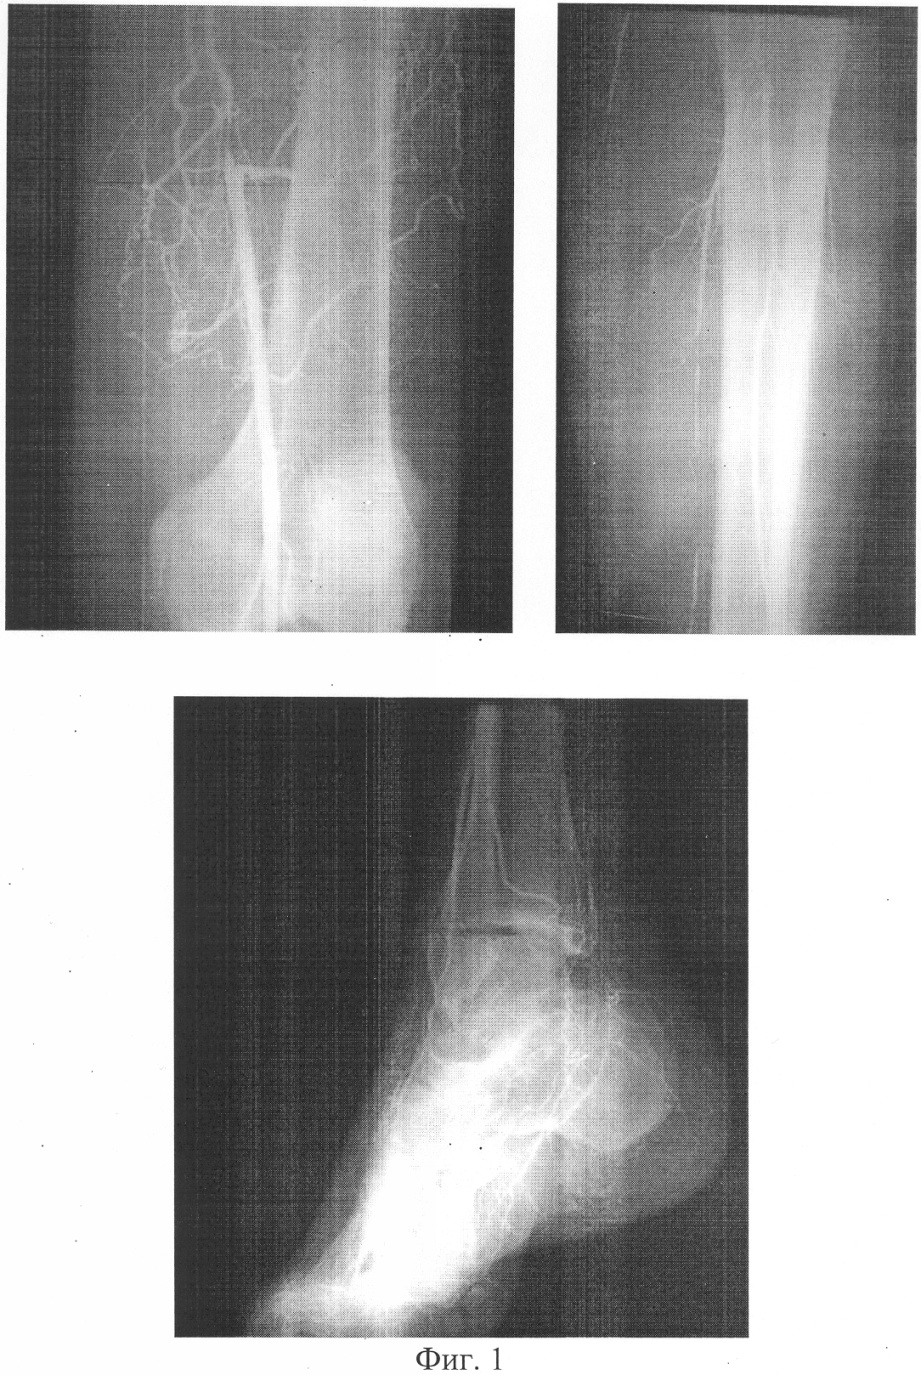

фиг 1. – артериограмма конечности больного Н. до лечения;

Больной Н. (фиг.1, 2) поступил в клинику с диагнозом: Сахарный диабет, II тип, субкомпенсация. Синдром диабетической стопы слева. Трофическая язва в области ампутированного II пальца левой стопы. Диабетическая ангиопатия. Перемежающаяся хромота через 150-200 метров. На артериограмме прослеживается локальная (4-5 см) окклюзия поверхностной бедренной артерии в средней трети, многочисленные стенотические поражения магистральных артерий на протяжении голени и стопы.

В послеоперационном периоде в течение 10 дней продолжали курс ранее назначенной медикаментозной терапии. Ранний послеоперационный период гладкий, швы на левом бедре сняты через 10 дней. Признаков тромбоза реконструированного участка артериального русла не отмечается. На артериограмме (фиг.3) определяется проходимая поверхностная бедренная артерия в зоне протезирования.